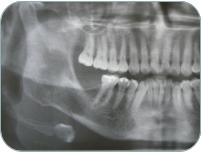

y diagnóstico usando exámenes clínicos,

radiográficos, microscópicos, así como el

manejo de la enfermedad.